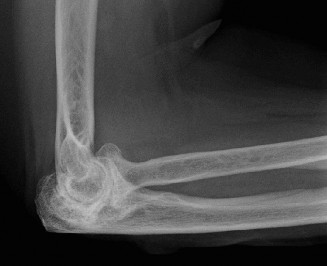

The correct answer is (E). Given that her rotator cuff has atrophied and has fatty infiltration to the point where there are equal parts fat and muscle, this is considered an irreparable rotator cuff tear. Repair should not be attempted because of poor outcomes following repair (see last two paragraphs of this discussion below). A reverse total shoulder arthroplasty is an alternative to repair that should be used in cases of massive, irreparable rotator cuff tears. It is a semi-constrained prosthesis that restores function in patients with massive rotator cuff tears by constraining a concave humeral cap inferior to a semispherical glenoid component (glenosphere). This creates an inferior force-couple and a fulcrum that replaces the stabilizing function of the infraspinatus maintaining a center of rotation around which the shoulder can move. This allows the deltoid to abduct and flex the shoulder without causing the humerus to migrate superiorly and about the acromion. In an elderly patient with a massive, irreparable rotator cuff tear (as in this patient), a reverse total shoulder arthroplasty is the procedure of choice.

It should be noted that reverse total shoulder arthroplasty is also the procedure of choice in patients with cuff-tear arthropathy (aka rotator cuff arthropathy). Characteristics of cuff-tear arthropathy include superior migration of the humerus due to a massive rotator cuff tear, glenohumeral joint destruction, subchondral osteoporosis, and humeral head collapse (see Fig. 2–17). A reverse total shoulder

Figure 2–17_X-rays of a patient showing evidence of cuff tear arthropathy. The humerus is migrated superiorly, the glenohumeral joint is destroyed, there is subchondral osteoporosis, and the humeral head is collapsed. (From Ecklund KJ, Lee TQ, Tibone J, Gupta R. Rotator cuff tear arthropathy. _J Am Acad Orthop Surg. 2007;15(6):340–349.)